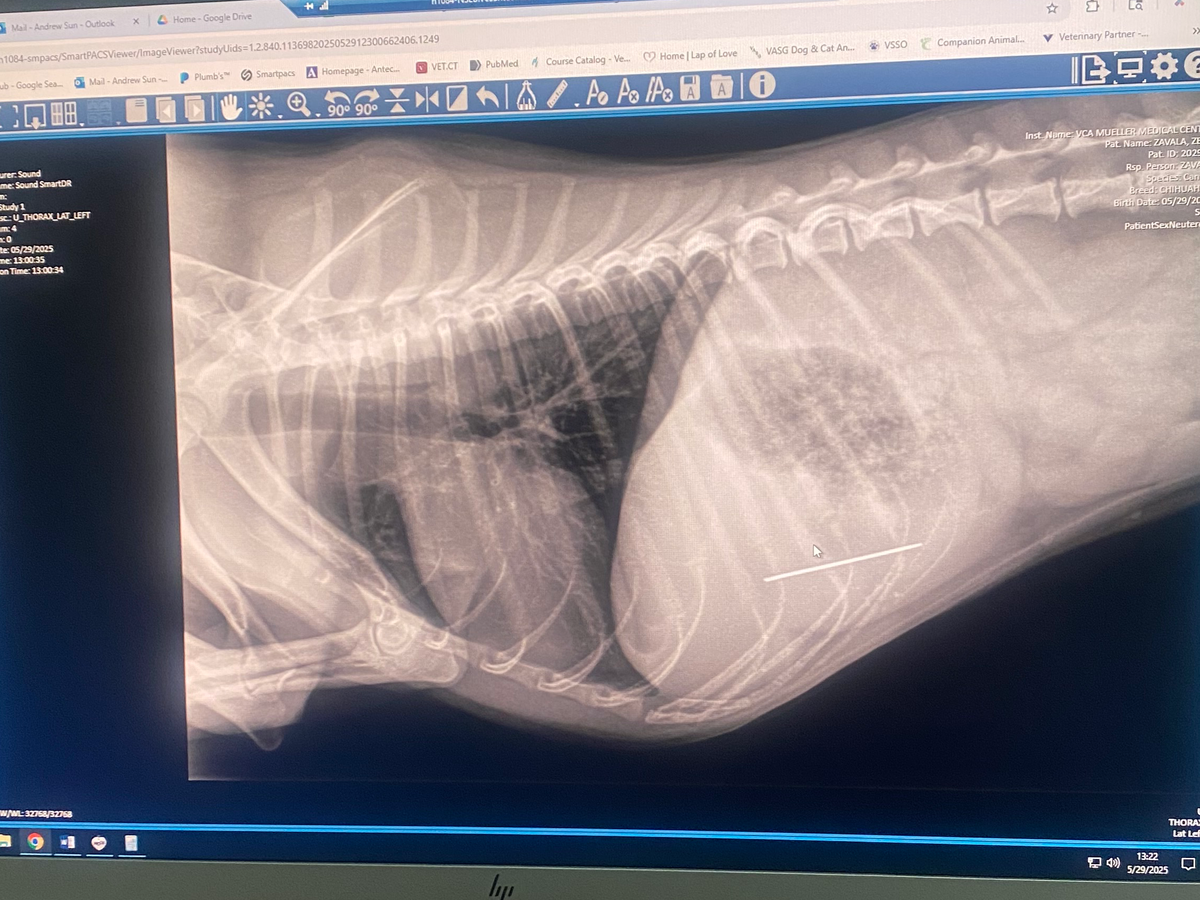

We rushed him to VCA Mueller Pet Medical Center in Sacramento, where they confirmed through X-rays that the needle is inside his body and surgery is the only way to prevent serious internal damage or worse. The estimate for his care and surgery ranges between $5,774.77 and $7,507.20 . As much as I wish I could cover this on my own, the cost is far beyond what I can afford right now.